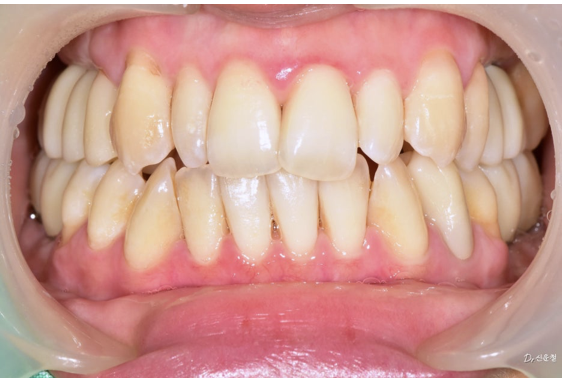

촬영일 : 250327

“사진 찍을 때 크게 못 웃겠어요.”

웃을 때는 앞니만 보이지 않습니다.

어금니까지 함께 보입니다.

앞니 배열만이 아니라 어금니 충치, 보철 색감, 잇몸 라인까지

전체적인 밸런스를 함께 봐야 합니다.

디에스다솜치과에서는

단순히 “보이는 앞니”만이 아니라

웃는 순간 전체가 자연스러운지를 기준으로 진단합니다.